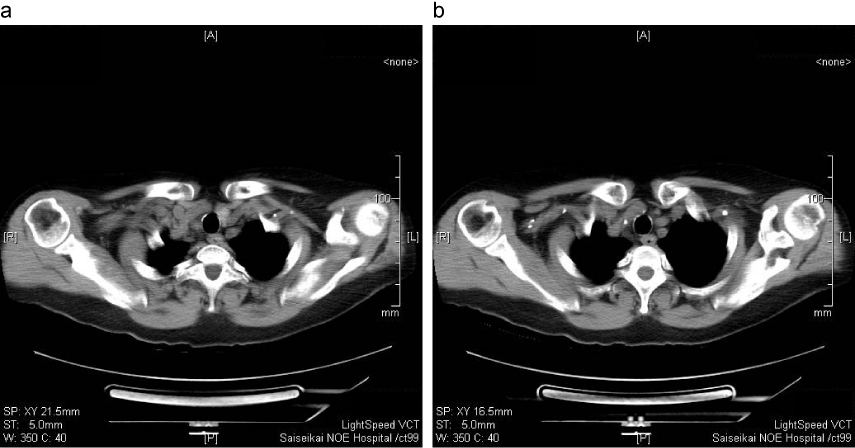

食道異物(PTP)例

a:食道入口部に異物(PTP)を認める。筋層深部に達し、周囲脂肪織の濃度上昇がみられ、炎症の波及が疑われる。

b:同上